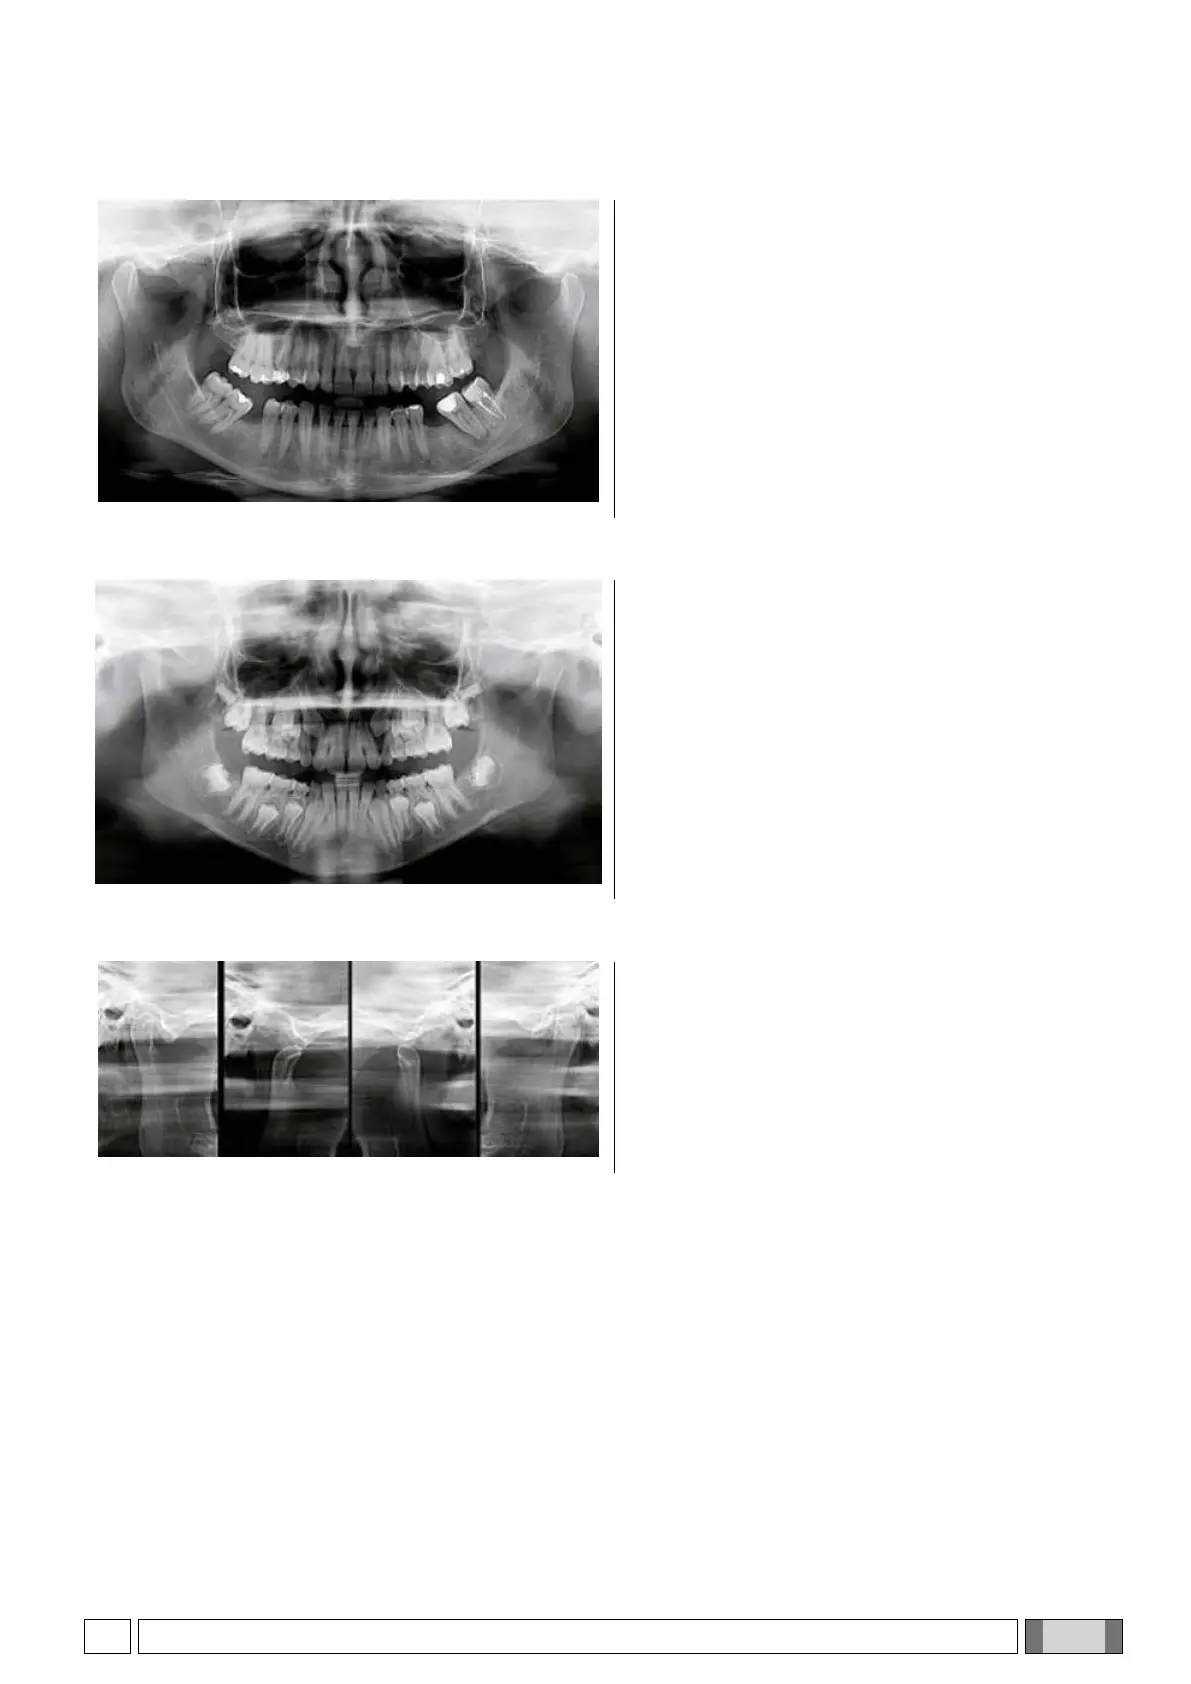

5.6. TYPICAL IMAGES OF THE EXAMS

5.6.1. ADULT PANORAMIC IMAGING

The program of standard panoramic exposure enables a

thorough or partial analysis of the patient’s state by

selecting the area of diagnostic relevance. The image on

the left shows a typical image with PAN standard

exposure.

5.6.2. CHILD PANORAMIC IMAGING

The program of standard panoramic child (PAN CHILD)

produce an automatically reduced and optimized

exposure that with a reduction in trajectory / time / dose

still allows the evaluation of the overall oral health of the

patient.

The image on the left shows a typical image with PAN

CHILD exposure.

5.6.3. TMJ EXAMINATIONS (TEMPOROMANDIBULAR JOINT)

The program for the X-ray of temporomandibular joints

(TMJ) allows a study of the temporomandibular status in

a simpler way showing four (latero-lateral and

posteroanterior) X-ray images in a single scan.

The image on the left shows a typical image with TMJ